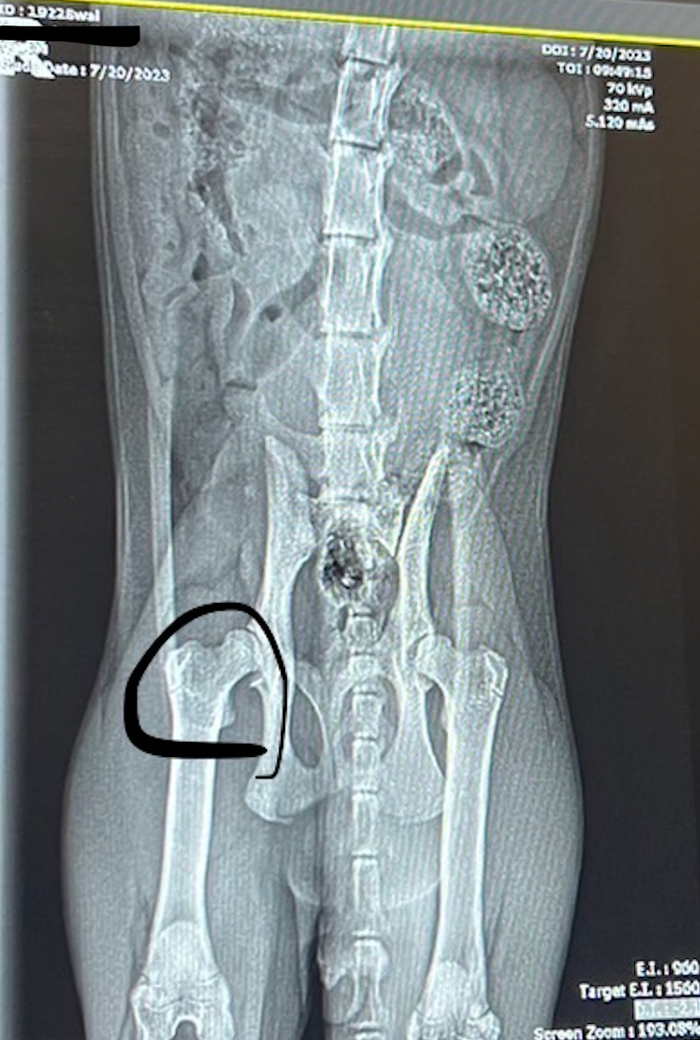

제 고양이는 10개월차이며, 대략 5-6주전부터 고양이가 앉을 때, 한쪽으로 약간 치우쳐서 앉는 모습이 보이기 시작했습니다. 여기 현지 수의사분께서 엑스레이를 보고, 동그라미로 표시되어 있는 골반에 약간 틈이 있다고 하는데, 나이가 들면서 염증을 일으키고 관절염이 발생할 수 있다고 합니다. 때문에, 한달에 한번씩 관절염 주사를 맞는 것이 좋다고 하셨는데, 어떻게 하는게 좋을까요?

혹시 엑스레이상에서 문제가 보이거나 그런게 있을까요?

해당 사진은 정자세가 아닌 rotation이 된 사진으로 해당 고관절의 아탈구 양상에 대한 평가를 해서는 안되는 사진입니다.

즉, 해당 수의사의 평가는 방사선 검사를 기초로 내린 결론이 아닌 촉진 즉, 만져보고 판단했을 가능성이 높습니다.

원칙에 입각한 진단을 하는 다른 동물병원으로 가서 다시 검사 받아 보시는걸 추천합니다.

그리고 만약 정말로 아탈구 상태라면 영양제나 식이 관리는 아무런 효과가 없고 관절염에 대한 약물 관리 후 악화될 경우 대퇴골두와 골목을 제거하는 수술을 시행할 필요가 있습니다. 하지만 지금 당장 고민할 부분은 아닙니다.